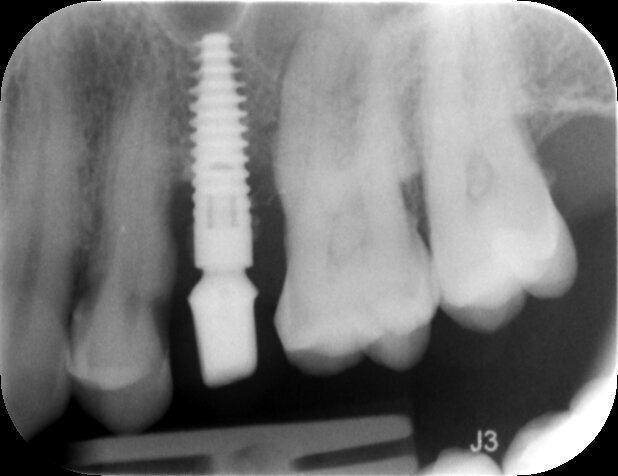

La paziente si presenta all’attenzione dello studio riferendo fastidi nella zona superiore sx, e all’anamnesi risultano trascorsi 3 anni dall’ultimo appuntamento di igiene presso altro centro. L’esame visivo e fotografico (Fig. 1) evidenziano un’alterazione dello stato dei tessuti perimplantari con sanguinamento spontaneo e lassità del tessuto molle, pertanto segue acquisizione di rx endorale da parte dell’odontoiatra (Fig. 2) da cui risulta un’importante riassorbimento osseo a carico dell’impianto. Segue un sondaggio perimplantare profondo (Fig 3), eseguito previa anestesia topica con Lidocaina 15%, per definire estensione e conformazione del difetto associandolo alla valutazione radiografica per la conta delle spire esposte.

Fig. 1

Fig. 2

Fig. 3

Si definisce un difetto con tipico aspetto a scodella, esteso a tutta l’area del perimpianto. Dalla sovrapposizione tra sondaggio ed esame radiografico, si evidenzia perdita del picco osseo distale all’elemento 14 indicando una prognosi peggiore dell’elemento implantare.